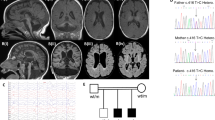

Pontocerebellar hypoplasia (PCH) is currently classified into 13 subgroups and many gene variants associated with PCH have been identified by next generation sequencing. PCH type 1 is a rare heterogeneous neurodegenerative disorder. The clinical presentation includes early-onset severe developmental delay, progressive motor neuronopathy, and cerebellar and pontine atrophy. Recently two variants in the EXOSC9 gene (MIM: 606180), NM_001034194.1: c.41T>C (p.Leu14Pro) and c.481C>T (p.Arg161*) were identified in four unrelated patients with PCH type 1D (PCH1D) (MIM: 618065). EXOSC9 encodes a component of the exosome complex, which is essential for correct processing and degradation of RNA. We report here two PCH1D families with biallelic EXOSC9 variants: c.239T>G (p.Leu80Arg) and c.484dupA (p.Arg162Lysfs*3) in one family and c.151G>C (p.Gly51Arg) in the other family. Although the patients studied here showed similar clinical features as previously described for PCH1D, relatively greater intellectual development (although still highly restricted) and normal pontine structure were recognized. Our findings expand the clinical consequences of biallelic EXOSC9 variants.